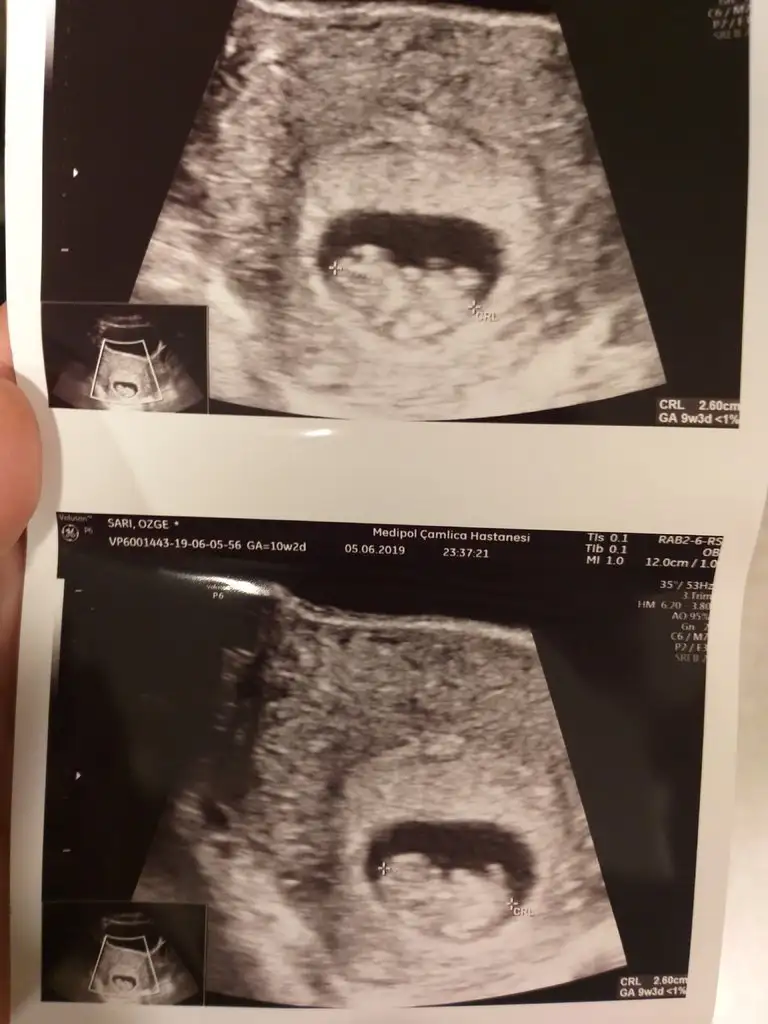

Canim bana gore erkek ama benim de bu sekilde bana kiz dedi burdaki arkadaslar suan 10+4gunluk olduk sabirsizlikla bende ogrenmeyi bekliyorum cuma kontrolum var tahmin istiycem dr dan soylerse InsallahHanımlar günaydın dün kontrole gittim 9+3 karından usg tahminlerinizi heyecanla bekliyorumEki Görüntüle 2276257

Hadi inşallah tahminde bulunursa beni de etiketle mutlaka cunku bende cok merak ediyorum bir an once ogreneyim sonra rahat edicemCanim bana gore erkek ama benim de bu sekilde bana kiz dedi burdaki arkadaslar suan 10+4gunluk olduk sabirsizlikla bende ogrenmeyi bekliyorum cuma kontrolum var tahmin istiycem dr dan soylerse Insallah

Tamm etiketliycemHadi inşallah tahminde bulunursa beni de etiketle mutlaka cunku bende cok merak ediyorum bir an once ogreneyim sonra rahat edicem

Canim resmi tatil diye bugunde dr yokmus ozel izin almis gorunemedim pazartesine kaldi artikHadi inşallah tahminde bulunursa beni de etiketle mutlaka cunku bende cok merak ediyorum bir an once ogreneyim sonra rahat edicem

Canim resmi tatil diye bugunde dr yokmus ozel izin almis gorunemedim pazartesine kaldi artik